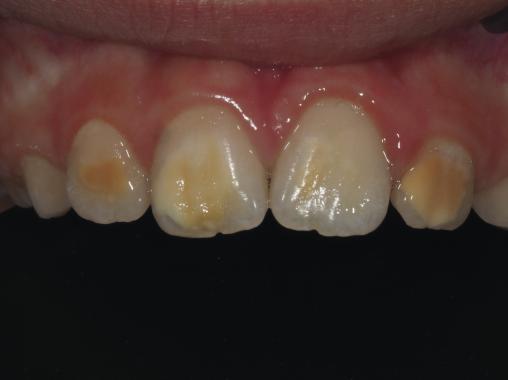

Atteintes MIH (molar incisor hypomineralisation) modérées à sévères sur des incisives permanentes maxillaires (dents n° 11, 12, 21, 22)